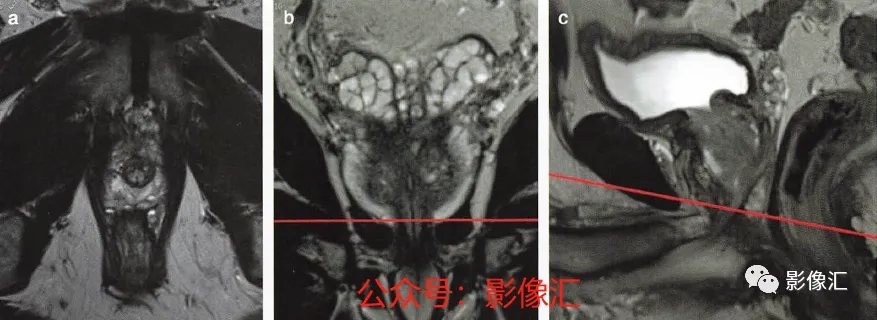

7. 前列腺下部水平的横轴面(图2.25)